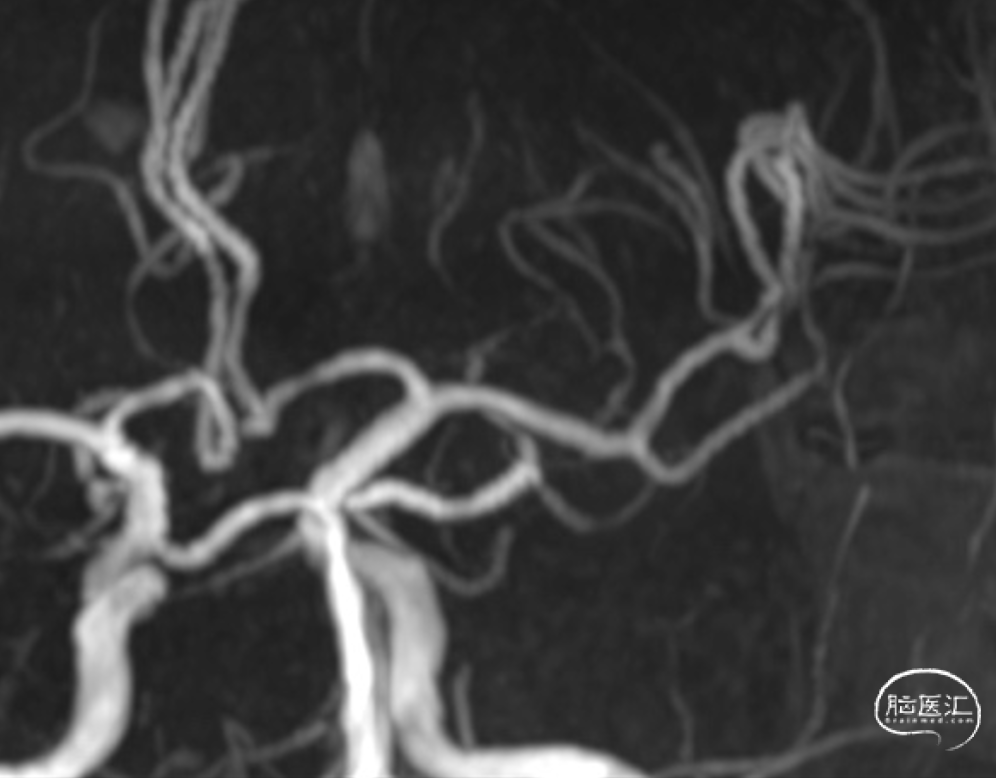

术前MRA造影

CTA提示左侧大脑中动脉M1段闭塞。

左侧颈内动脉造影明确大脑中动脉M1段闭塞。